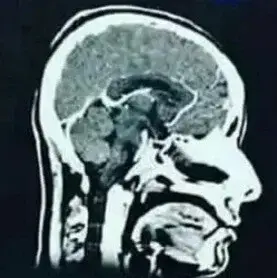

MRI scan (Magnetic Resonance Imaging) is a magnetic resonance scan. The MRI scan uses a magnetic field that is harmless, except if there are iron objects in the body or on the body. An MRI scan consists of a table on which the patient lies and a hollow cylindrical magnet. The cylinder is too frightening for many people and people who are seriously overweight do not fit in it. That is why MRIs are also made with two separate plates.

An MRI scan can show how many hydrogen nuclei are in one area. Each type of tissue has different hydrogen densities and thus details of the anatomy can be observed. A three-dimensional image is formed from the measurements.

An MRI scan can observe the brain structure, location, size, space-occupying processes, (brain tumors and inflammations) abnormalities of healthy tissue and scars (focal damage). An MRI scan cannot show axonal damage or diffuse axonal damage, or the latter with great difficulty as a white matter abnormality.